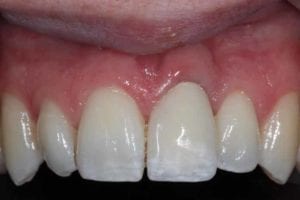

Trauma to Upper Front Teeth

Both central incisors were broken, leaving just the roots. Unfortunately, there wasn’t enough tooth to repair these teeth and they were subsequently removed. Dental implants were placed to restore the missing teeth.